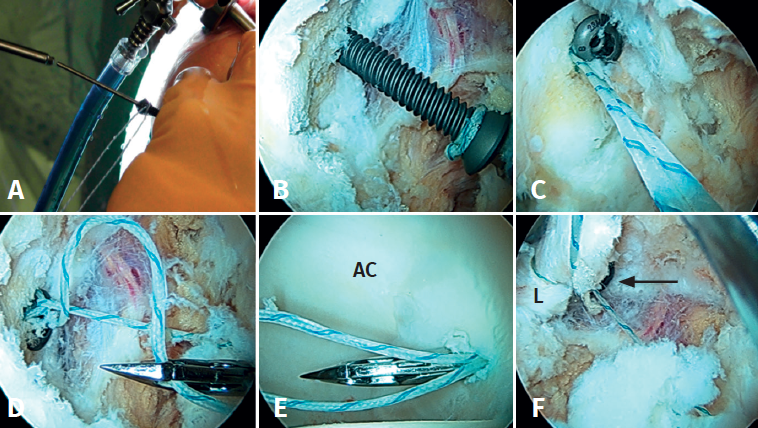

- Tratamiento: dependiendo de la cobertura que quede tras la extirpación, se decidirá si enuclear el fragmento o fijarlo. La planificación preoperatoria es por tanto crucial para garantizar que la escisión de la fractura/fragmento no dé como resultado una cobertura insuficiente o una inestabilidad iatrogénica. La medición del ángulo centro borde lateral y anterior al nivel de la extirpación planificada puede dar una indicación de una cobertura insuficiente resultante si el fragmento contribuye a la estabilidad de la cadera. En estos casos, debe considerarse la fijación quirúrgica mediante fijación con tornillo canulado asistida por artroscopia a través de la unión fibrocartilaginosa(4). En casos de fragmentos grandes que contribuyan simultáneamente al pinzamiento y la estabilidad, se puede realizar resección parcial y fijación del remanente. La utilización de una sutura sobre el tornillo de fijación ayudará a realizar la fijación labral sin tener que usar un arpón o anclaje(4)(Figura 4).